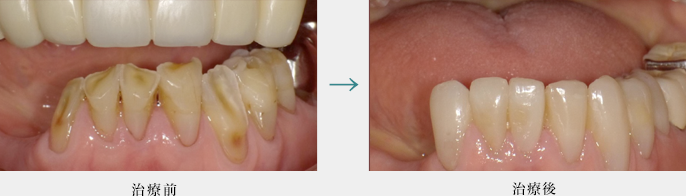

ダイレクトボンディング

ダイレクトボンディングによる健全な歯質を温存した虫歯治療(前歯)

健全な歯質は削らず物性に優れた樹脂を詰めています